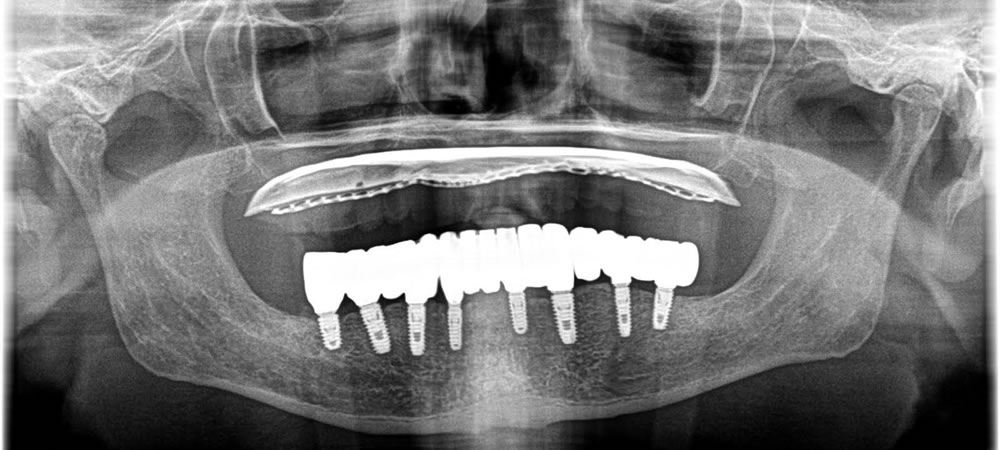

インプラントの本数としては、強度的にも心配という事で8本を希望されました。

上部構造の作成・装着

埋入後はフィクスチャーと、骨がオステオインテグレーションするのを待ち、しっかりとくっついている事を確認し、上部に歯を作成していきました。

治療完了

噛み合わせや歯並び、歯の長さを測り、審美的に綺麗になるように作成する事ができました。結果、見た目の改善、咬合の改善をする事ができ、しっかりと食事をする事ができるようになりました。